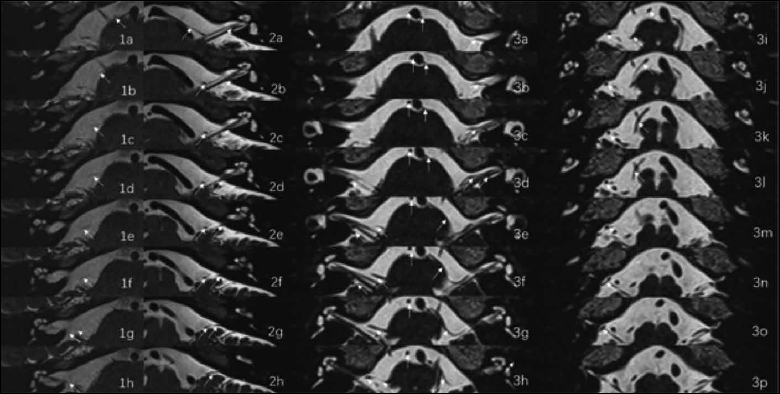

Figure 1. Kazawa classification of anterior inferior cerebellopontine artery (AICA) loop. (1a-h) Type IA in which nonloop AICA (arrow) in the cistern; (2a-h) Type IB in which nonloop AICA (arrow) into the internal auditory canal (IAC); (3a-p) Type IIA (right side) in which loop type AICA (arrow) in the cerebellopontine angle (CPA) cistern and type IIB (left side) in which loop type AICA (arrow) enters the IAC.